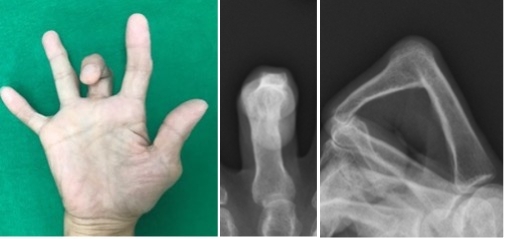

関節リウマチ患者に対する腱移行および手関節形成術

手関節の変形により腱断裂(特に伸筋腱)が生じ、急に指が伸びなくなる患者さんがいます。小指から始まり、比較的早期に手術をしない薬指中指と断裂が進行します。

断裂が進行しないように手関節の形成と、切れた腱に対しては直接縫合することは困難なため、隣接する正常な腱を用いて腱移行や腱移植を行ないます。

術前(写真)

術後(写真)

術前(レントゲン)

術後(レントゲン)

手術前の指の伸展不足が改善しています